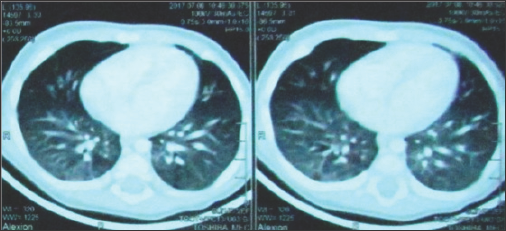

A 9 and 8 months old male infants; presented to our emergency unit (at two different occasions) within few hours after history of F.B swallow (Okra pods) given by their guardians with quite similar presentations like the first case. Immediate endoscopic extraction was done and Okra pod was successfully removed in both cases. In the third case, Okra was partially lodged in the nasopharynx (Figure 1) ; so, it was cut by scissors and removed in two pieces. After removal, examination revealed minor mucosal erosions (Figure 2) . Postoperatively, both infants were transferred to PICU. CXR and CT chest were done and revealed ground-glass opacity with interlobular sepal thickening in the middle and lower lobes of both lungs (Figure 3). Aspiration pneumonia was diagnosed. Treatment regimen included systemic steroid, oxygen therapy, antibiotics and raceme nebulizer. Marked improvement of their chest condition up for one month then monthly for 3 months revealed nothing was observed and oral feeding started within 2 days. They were abnormal as regard their clinical and radiological examination [1]. discharged one week after PICU admission. Regular weekly follow up for one month then monthly for 3 months revealed nothing abnormal as regard their clinical and radiological examination [1].

Figure 3: CT chest showing ground-glass opacity with interlobular sepal thickening.

Diagnosis is based on a history of oil exposure, characteristic radiological endings, and presence of lipid-laden macrophages on sputum or bronchi alveolar ravage (BAL) [8]. Clinical manifestations of LP are greatly different, depending upon tissue reaction to exogenous lipid, quantity and, duration of aspiration and host lung conditions [9]. CT imaging is the clue for diagnosis. Radiological features include air-space consolidation, interstitial infiltrates, ground-glass attenuation with or without superimposed sepal thickening and air-space nodules [10]. The best treatment is removal of the offending agent. Aggressive therapies are recommended in cases with severe pulmonary damage, including systemic steroids and BAL in neglected cases [8]. We reported three cases of acute ELP due to aspiration of oil components released from Okra pods. It is a serious condition that might be fatal if not managed promptly due to respiratory failure which was the scenario in the first case.